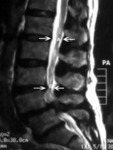

ოსტეომიელიტის მაგნიტურ-რეზონანსული კვლევა: T11-T12 დისკების სივრცე დაზიანებულია დისკის ანთებასთან ერთად (A). აღინიშნება ორივე მალის ძვლოვანი დაზიანება,რაზეც მიუთითებს მაღალი T2 სიგნალი მალების სხეულებზე. ისრით მითითებულია ნორმალური, დაუზიანებელი მალის დისკი

ექიმ Dr K. Singh საკუთრება; გამოყენებულია ნებართვით